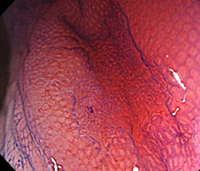

C:色素撒布像によって病変が明瞭化する。

-

D:ピオクタニン染色下拡大観察像で、内視鏡切除可能と判断。